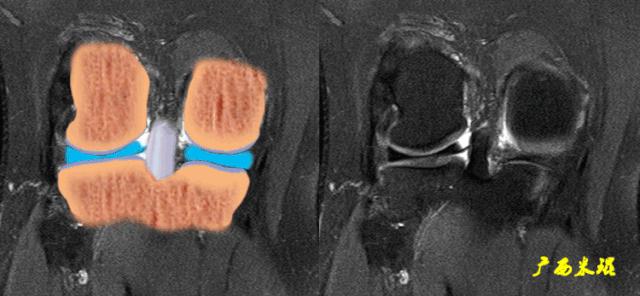

3、冠状面表现

冠状面PCL表现为较宽的带状均匀低信号影,边缘清晰,内部纹理清楚。